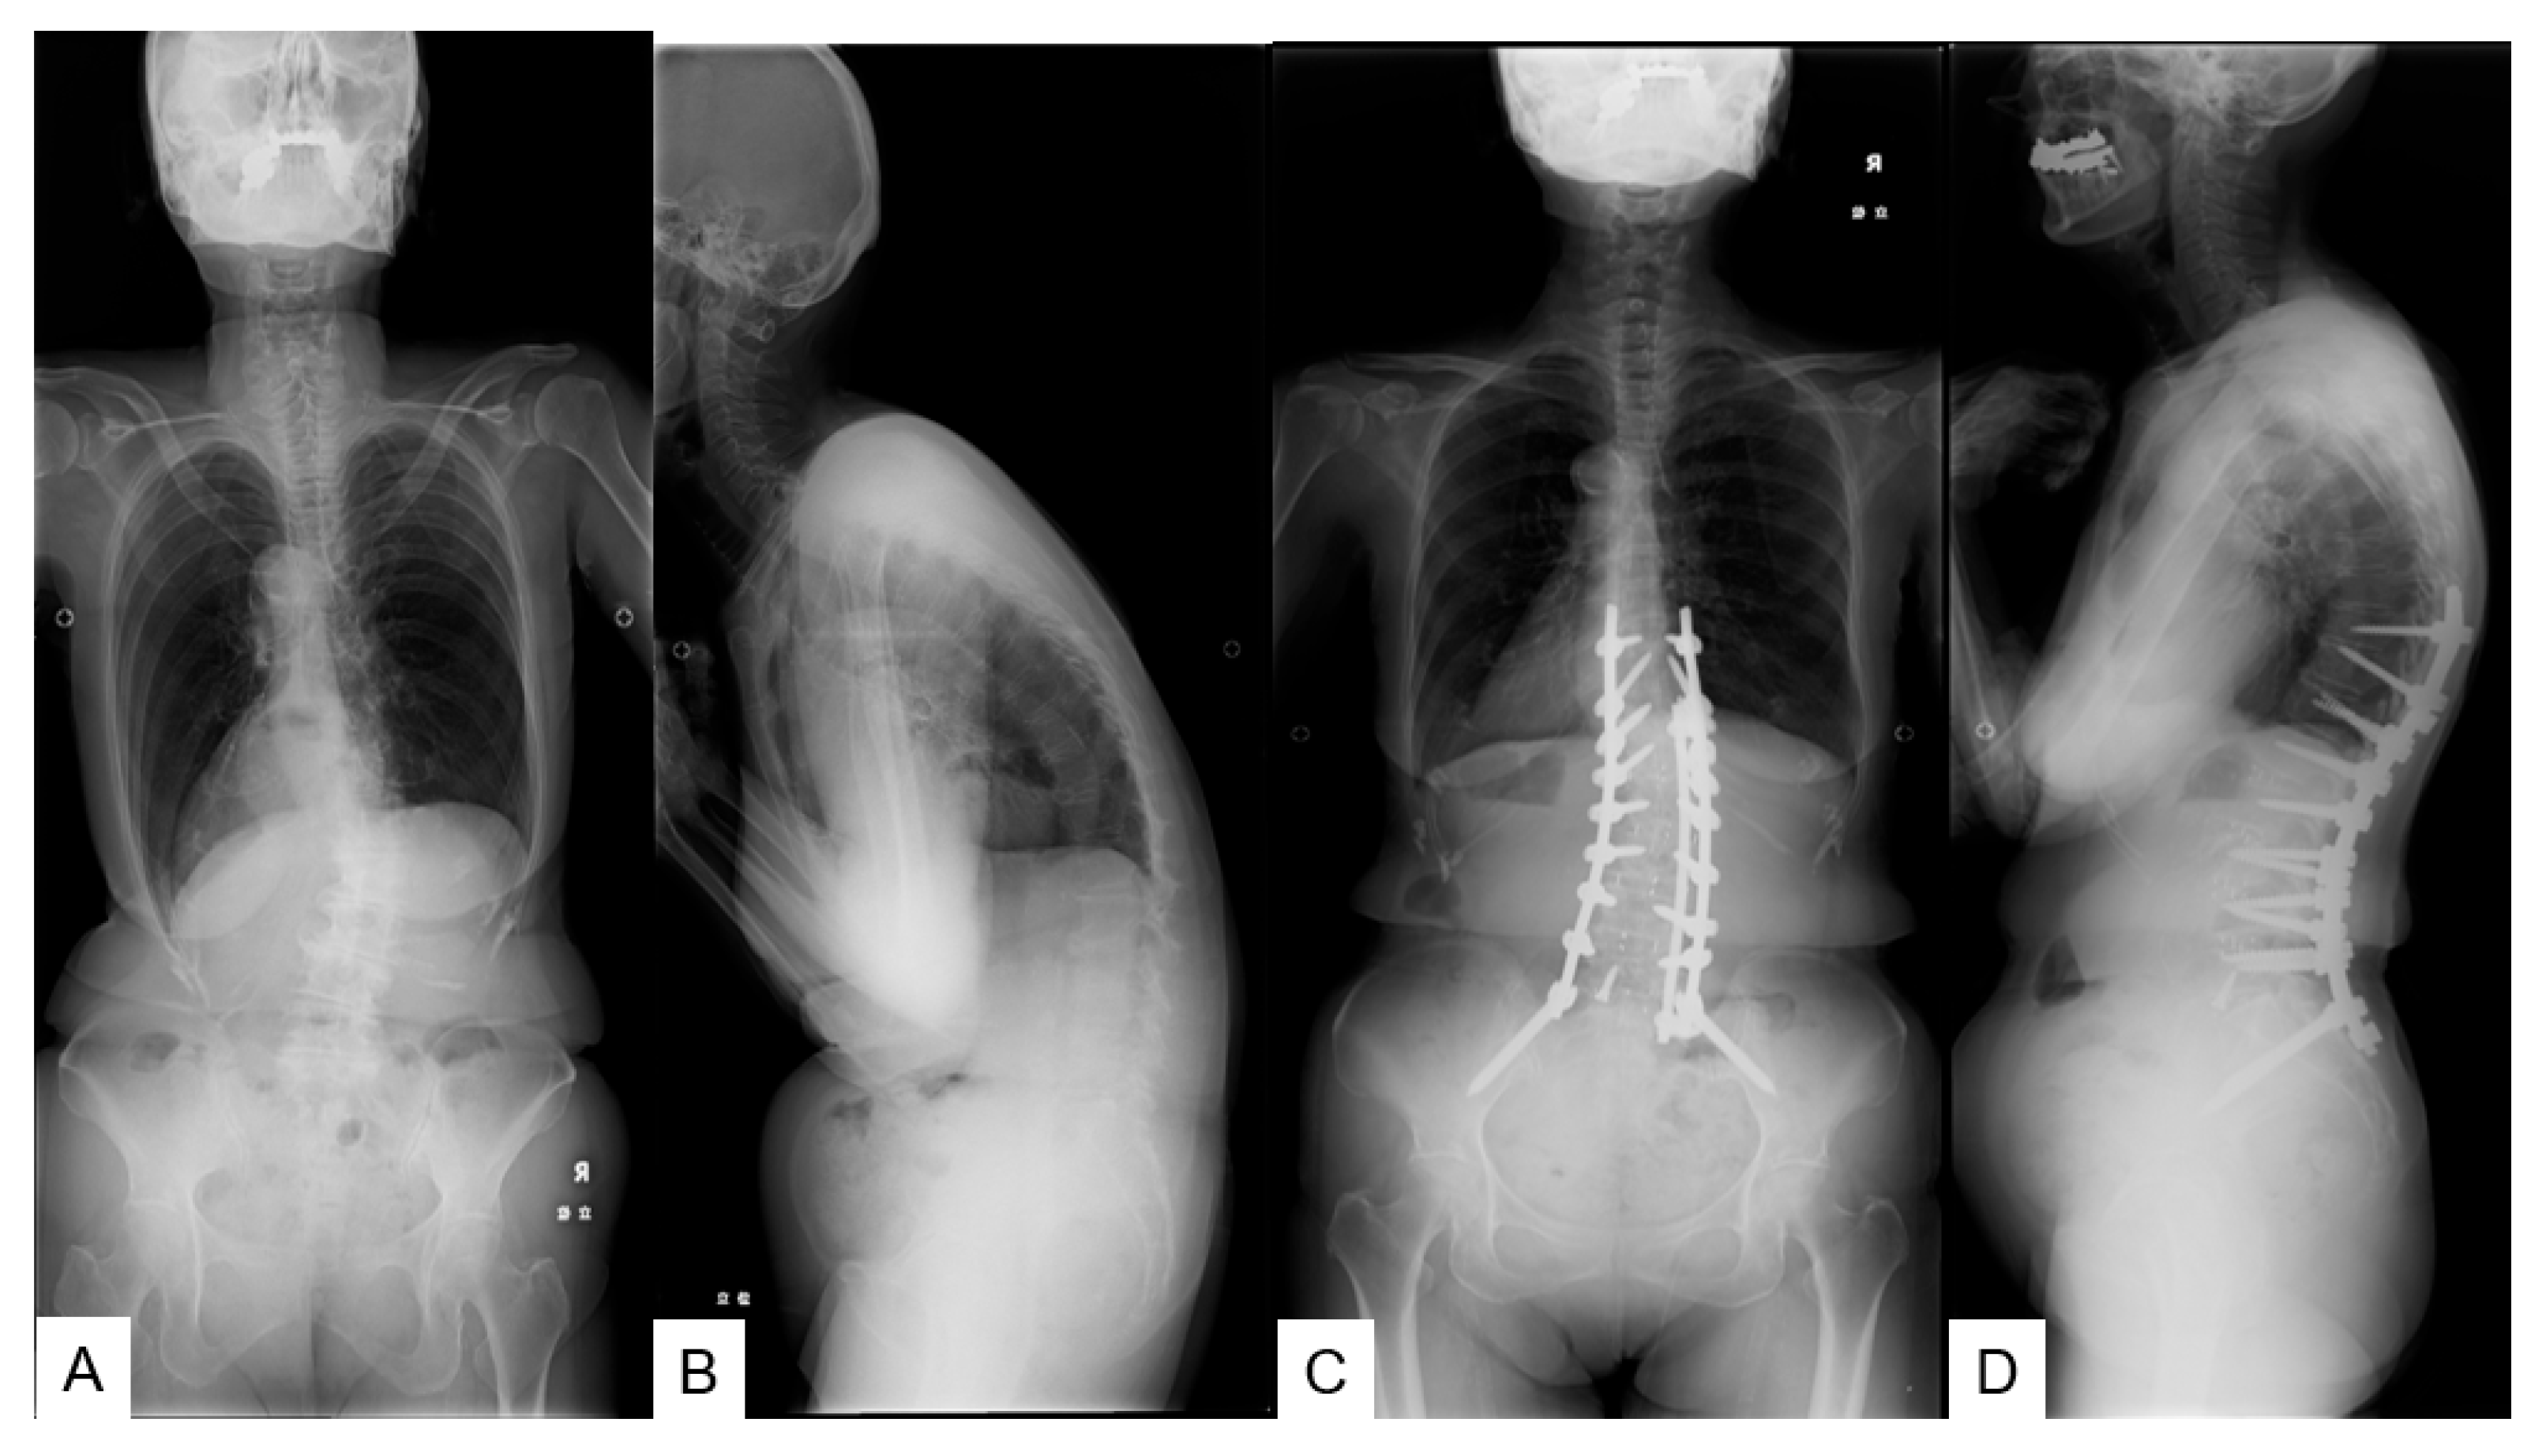

2. Materials and Methods

2.1. Patient Demographics

2.3. Radiographic Measurements